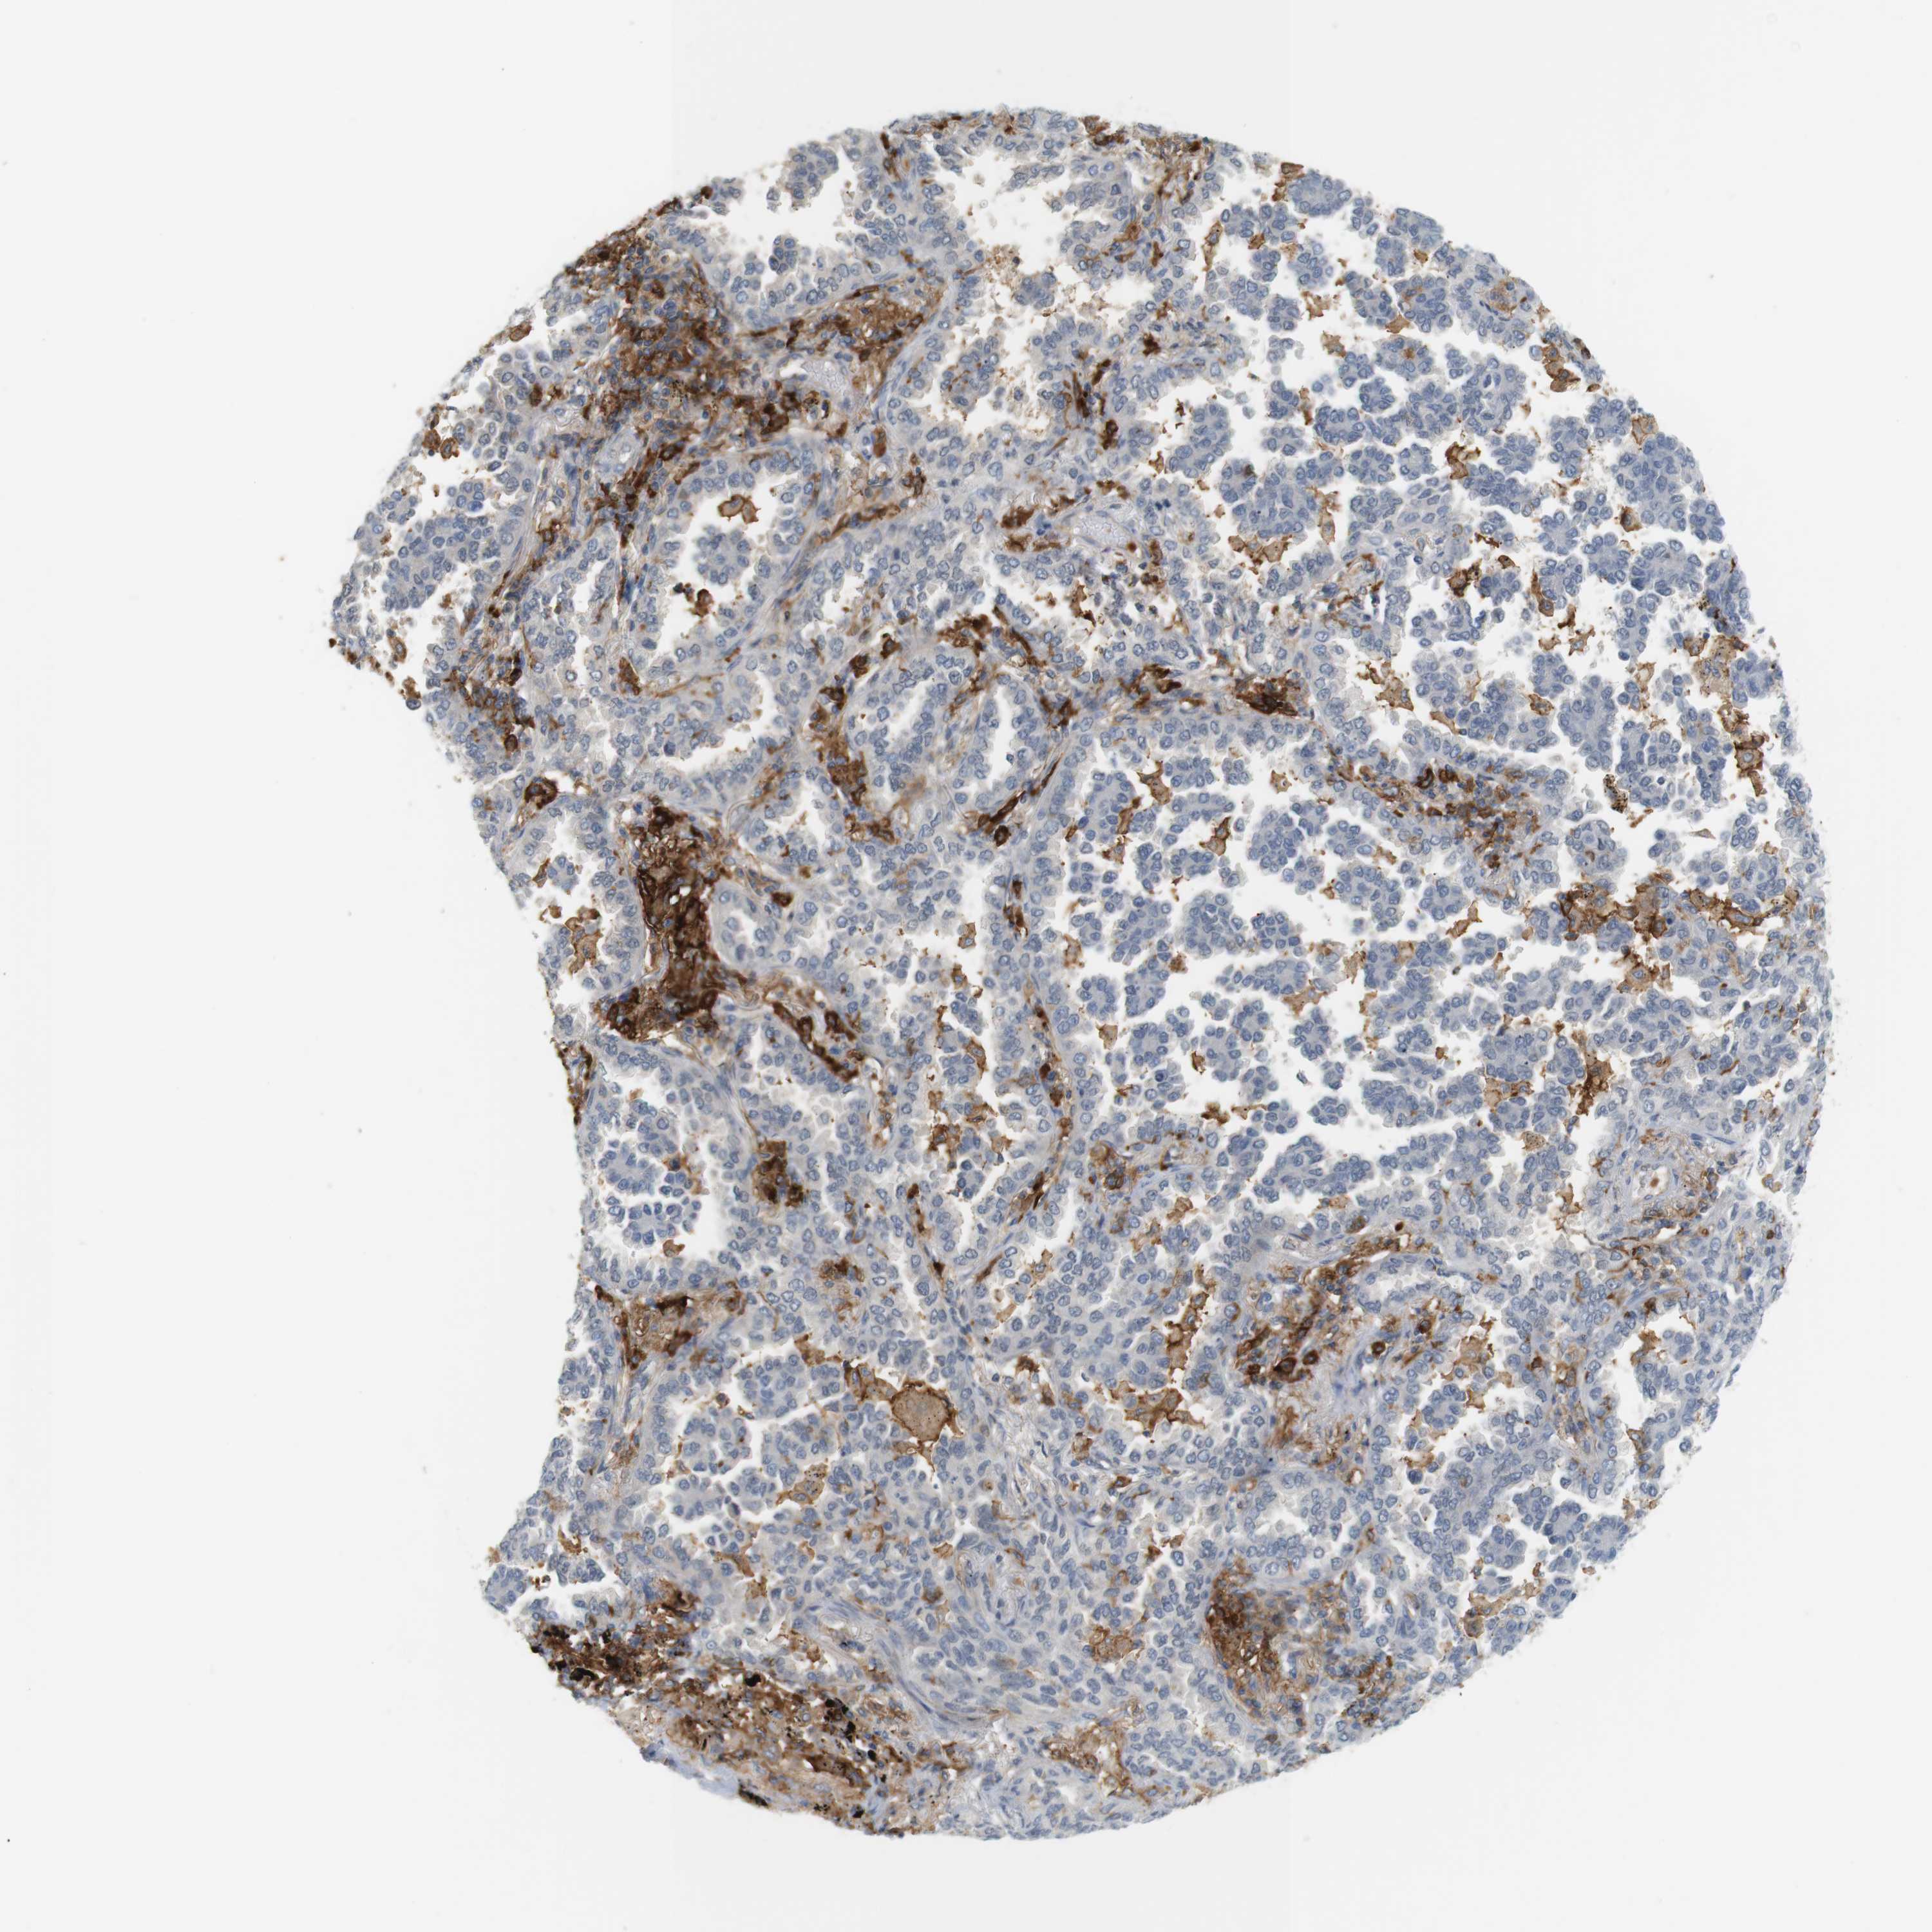

CANCER LUNG CANCER Show tissue menu

LUAD TCGA LUAD VALIDATION LUSC TCGA LUSC VALIDATION PROTEIN LUAD CPTAC PROTEIN LUSC CPTAC PROTEIN EXPRESSION